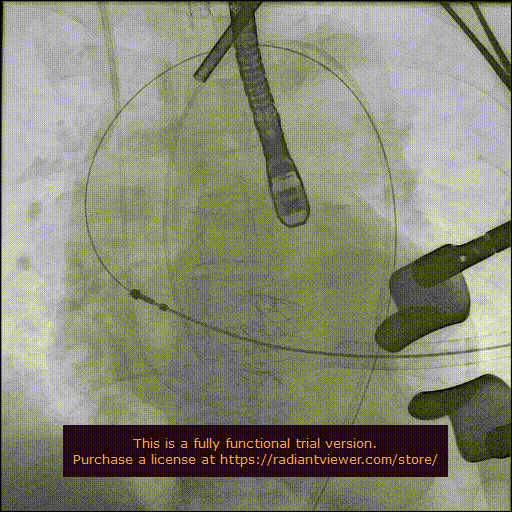

经心尖途径置入 J-Valve 瓣膜输送系统,在升主动脉部打开定位件,调整角度,轻轻向后牵拉输送器使定位件进入主动脉窦内。联合主动脉根部造影和食管超声观看定位件是否定位于窦底,形态随着心脏跳动而自然摆动即可。下降瓣膜至主动脉瓣环内,在主动脉瓣口释放瓣膜支架,此过程无需快速起搏。瓣膜成功释放后移除瓣膜输送系统。行主动脉根部造影及经食管超声检查,对瓣膜功能、位置情况进行术后即刻评估。确认位置良好、功能正常后,移除导丝及输送系统,并收紧心尖荷包缝线打结固定。

最后再次血管造影确认介入瓣膜位置稳定,活动良好,无瓣周漏,冠状动脉开口无阻塞。

释放瓣膜

造影确认瓣膜位置

撤出输送系统

造影确认植入效果